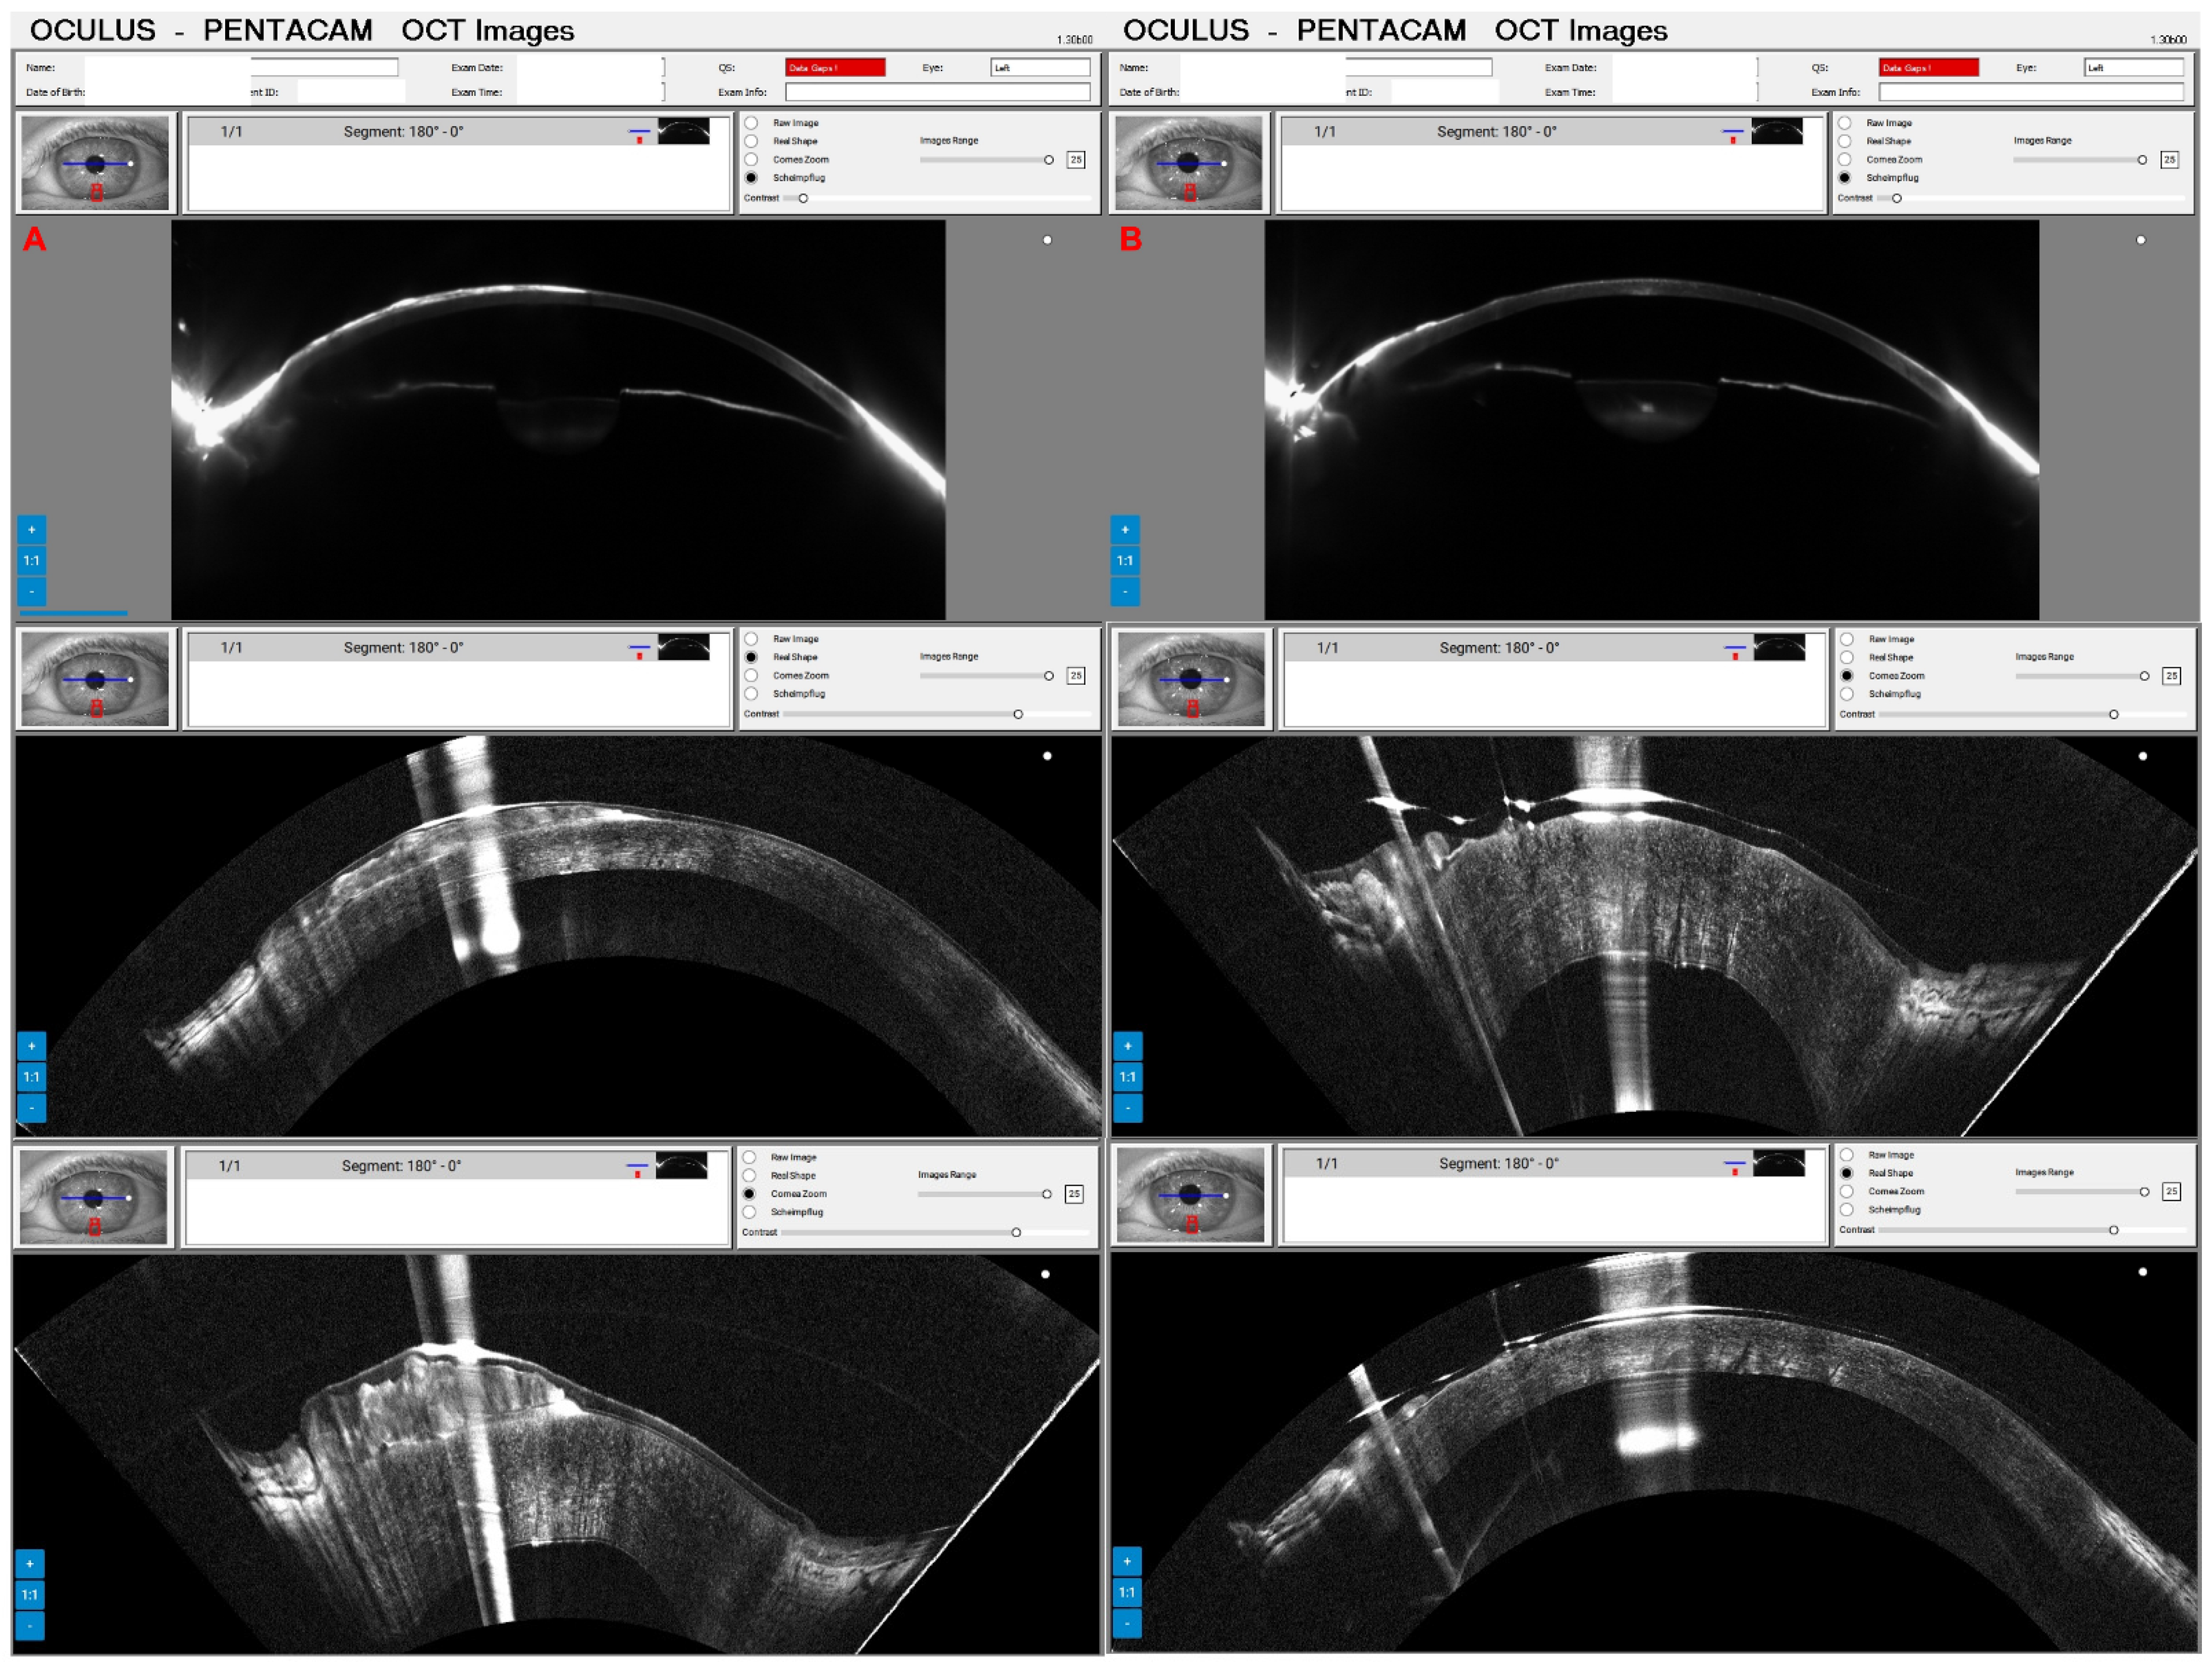

Combined Rotating Ultra-High-Resolution Spectral Domain OCT and Scheimpflug Imaging for In Vivo Corneal Optical Biopsy

1.3. The Pentacam® Cornea OCT

2. Materials and Methods

3. Results